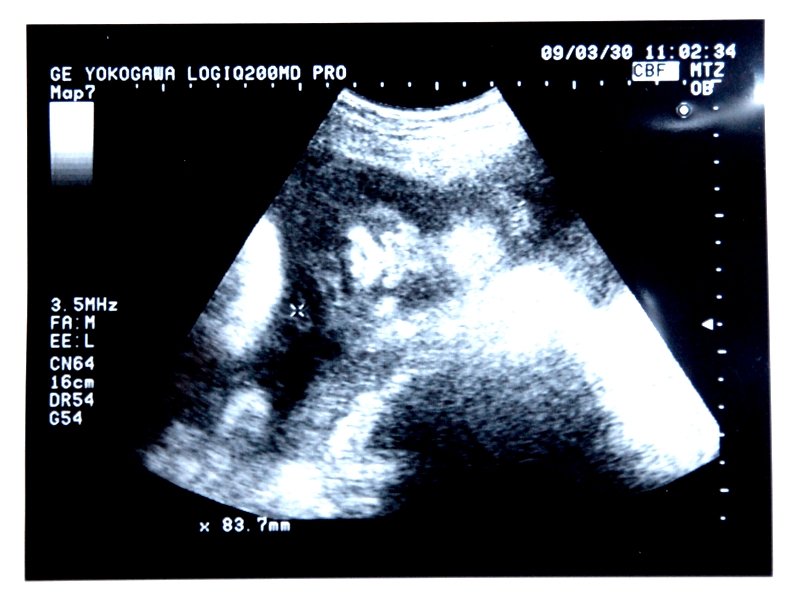

妊婦健診は1週間に1回になります。発育ぶりを確認するとともに、この時期のサイズ測定は、産道を難なく通り抜けられるかどうか、難産のリスクが高くないかを判断する大切なものです。